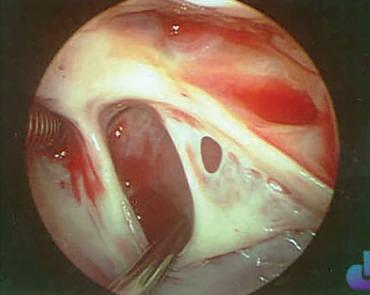

Vídeo 7.3.9

Este vídeo demonstra claramente a devastação causada pela infeção num caso de endocardite bacteriana aguda protésica aórtica e o seu tratamento. Disponível em: https:// www.youtube.com/watch?v=Kekr8zLeSqg. Consultado a 2 de agosto de 2023.